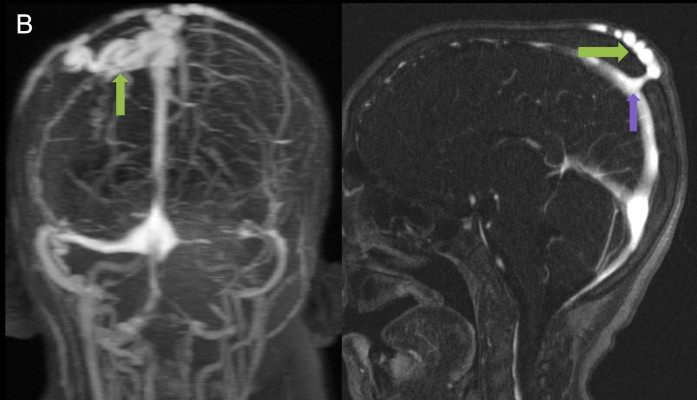

2. B) Kontrastlı MR venografide orta hatta cilt altı dilate (oklar), tortiyoze emisserian vaskuler yapıların superior sagital sinus ile ilişkisi ve devamlılığı (ok) izlenmektedir.